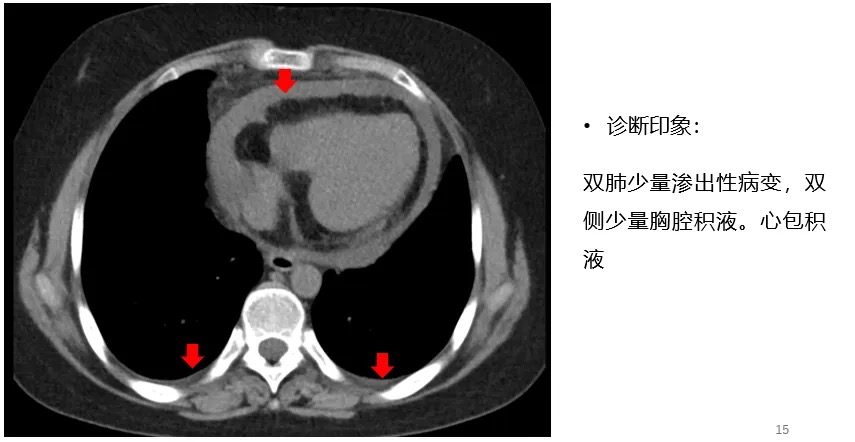

治疗期间肺CT变化

29岁青年女性,慢性病程急性发作,以间断发热、胸痛为主。查体,体温升高,最高38℃,心动过速,没有心包摩擦音,心音低钝,心电图提示广泛导联ST-T段改变。心脏超声提示少到中量心包积液及渗出。肺CT提示心包积液,心包增厚。根据指南,心包炎诊断需满足以下4条中的任意2条:胸痛、心包摩擦音、心电图改变、心包积液。结合患者的症状、体征及辅助检查,心包炎诊断成立,排除冠心病、胸膜炎、易栓症诊断。